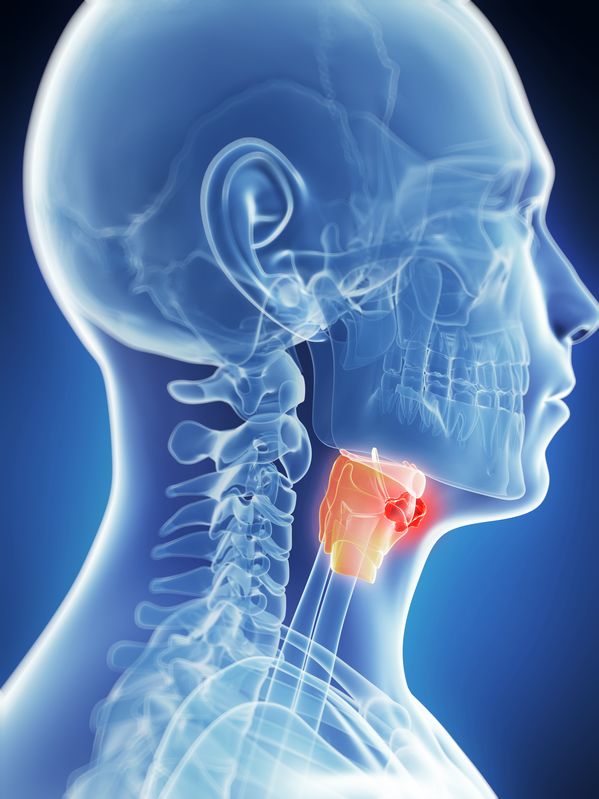

Laryngectomie is een operatie waarbij de chirurg het gehele strottenhoofd (larynx), de stembanden inbegrepen, wegneemt. In de larynx kunnen zowel goedaardige als kwaadaardige gezwellen voorkomen, hetzij op de stembanden of op de slijmvliezen rond de stembanden.

Aanhoudende heesheid, ademnood, slepende hoest of een knobbeltje in de hals vormen alarmsignalen. Naarmate het gezwel groeit kan dit ademhalingsmoeilijkheden, slikproblemen en gewichtsverlies uitlokken. Als deze symptomen zich voordoen moet men dringend een geneesheer raadplegen.

Gevolgen van een operatie met totale laryngectomie.